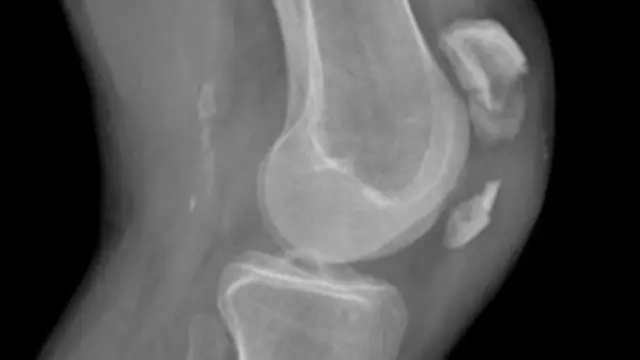

အရိုး အစားထိုး ကုသတဲ့ နေရာမှာ သက်ရှိ အရိုး ဖြစ်အောင် ထုတ်လုပ်ပြီး လူတွေမှာ ကုသ နိုင်တော့မယ် ဆိုတဲ့ အကြောင်း ကူးတက် နည်းပညာ ကမ္ဘာထဲ ကနေ လေ့လာ တင်ဆက်ထား ပါတယ်။

အရိုး အစားထိုး နိုင်ဖို့ ခန္ဓာကိုယ် ထဲ တနေရာ ကနေ အရိုးကို ဖဲ့ယူပြီး လိုအပ်တဲ့ တခြား နေရာမှာ အစားထိုး ရတာ ဖြစ်ပါတယ်။

ကြီးကြီး မားမား ထိခိုက်လို့ အရိုး အများကြီး ပျက်ဆီး ဆုံးရှုံးရ တာမျိုးနဲ့ မွေးရာပါ အရိုးလို အပ်နေတဲ့ သူတွေ အတွက်၊ အခု နည်းပညာ ကနေ ဖြည့်ဆည်း ပေး နိုင်တော့ မှာ ဖြစ်ပါတယ်။